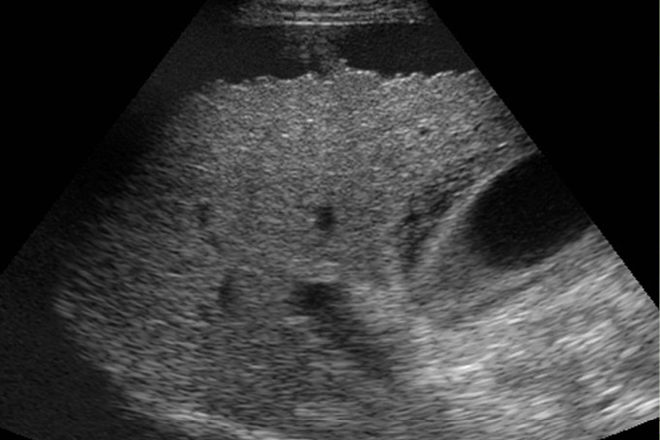

Nefrocalcinosis en pacientes con mutaciones recesivas del INSR

Antecedentes / Objetivos: Los síndromes Donohue y Rabson-Mendenhall son raros trastornos recesivos autosómicos causados por mutaciones en el gen receptor de insulina, INSR. Cuyas características fenotípicas incluyen resistencia a la insulina extrema, retraso del crecimiento lineal, escasez de grasa y músculo, y el crecimiento excesivo